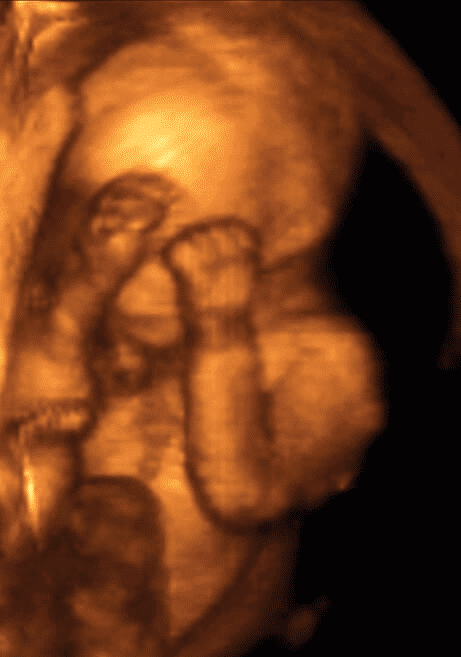

Фото Ребенка На 19 Неделе